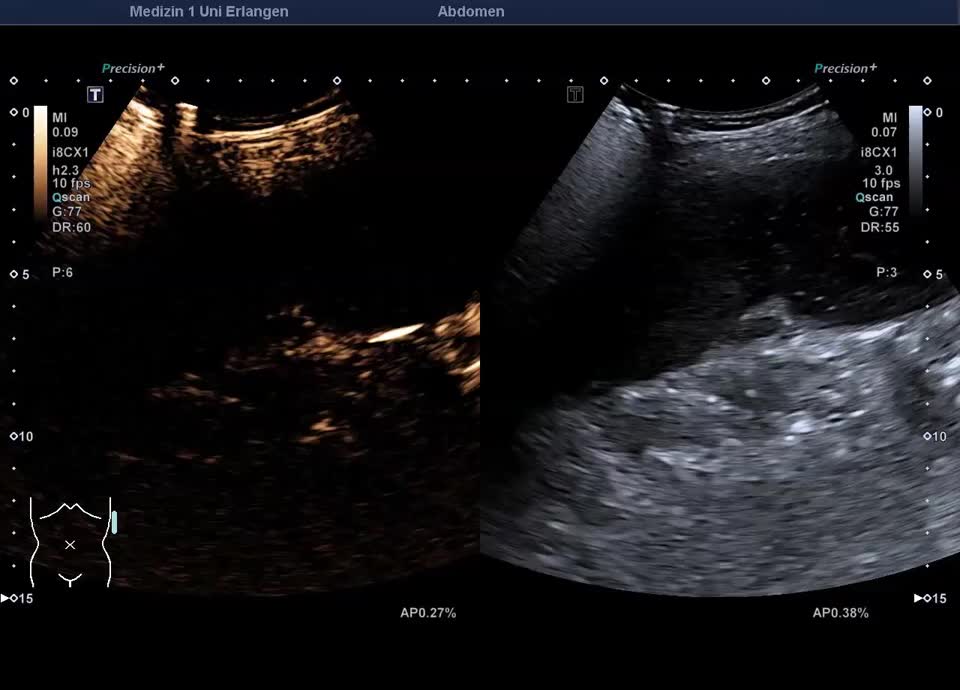

Epikrise: 19-jährige Patientin mit einem schweren angeborenen Herzfehler berichtet über plötzlich aufgetretene starke Schmerzen in der linken Flanke vor 14 Tagen. Sonographisch zeigt sich die Milz regelrecht lokalisiert, mit einem ausgedehnten Milzinfarkt der unteren Milzhälfte. Weder im Farbdoppler, noch im CEUS, lässt sich eine Restperfusion der unteren Milzhälfte feststellen. Therapeutisch wird eine Antikoagualtion begonnen und eine Verlaufskontrolle in 4 Wochen veranlasst.